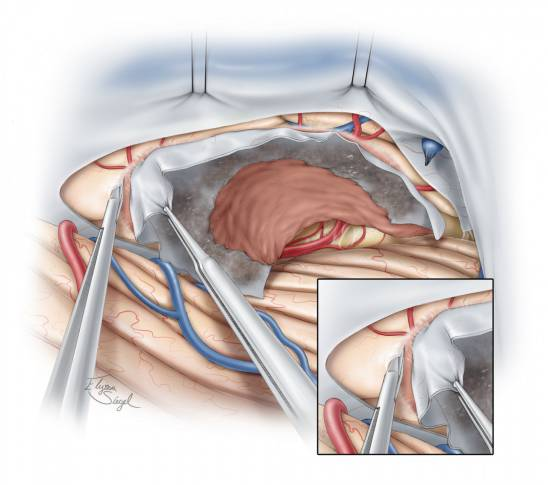

图6. 在切开天幕接近肿瘤的过程中,可通过锐性分离蛛网膜来充分暴露天幕游离缘的神经血管结构,早期的充分暴露能够避免在肿瘤切除过程中受到损伤。

充分锐性分离瘤旁的蛛网膜带会避免损伤滑车神经。

图7. 识别天幕游离缘旁的滑车神经。将位于天幕缘旁的滑车神经及周围血管结构充分游离并保护起来,如果可行,先将这部分肿瘤减容。天幕游离缘附近的脑干背外侧神经神经血管结构要在大规模切除肿瘤之前充分暴露,以免切除过程中由于视野不清误伤。